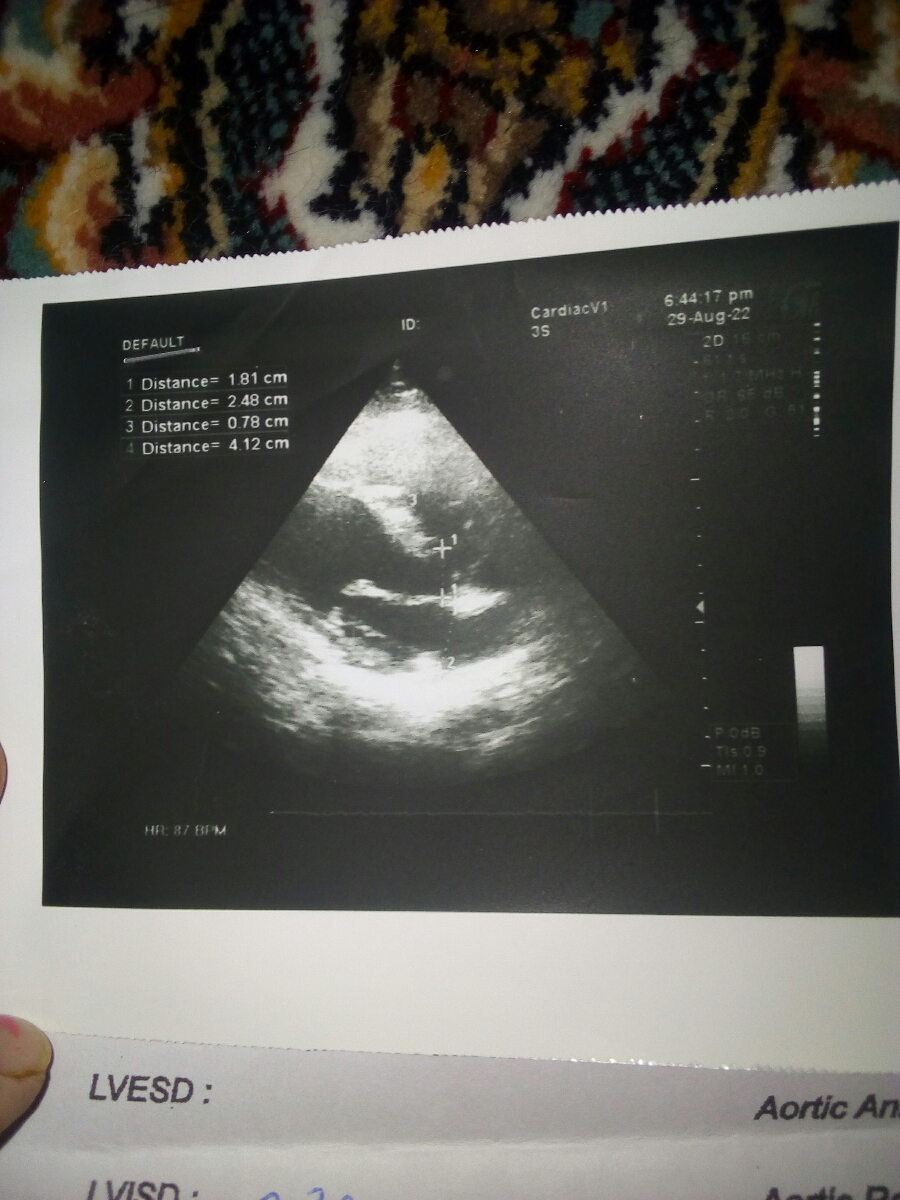

اینم عکس اکو